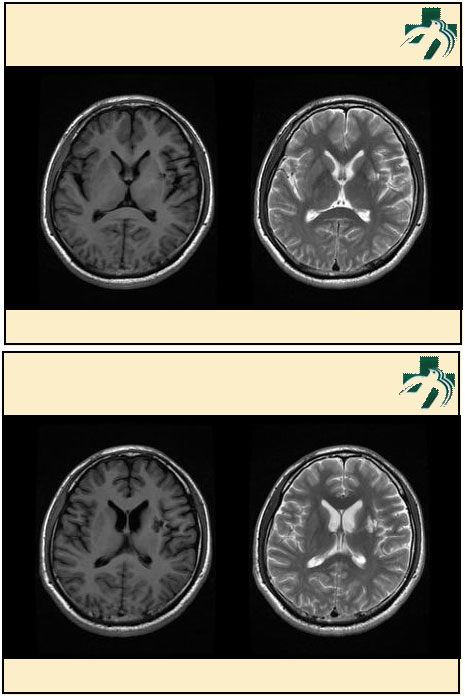

奴卡氏菌感染

第九期三博

读片会

病例之四

北京协和医院 提供

男性,22岁。自觉虫咬后皮疹、肢体麻木4月